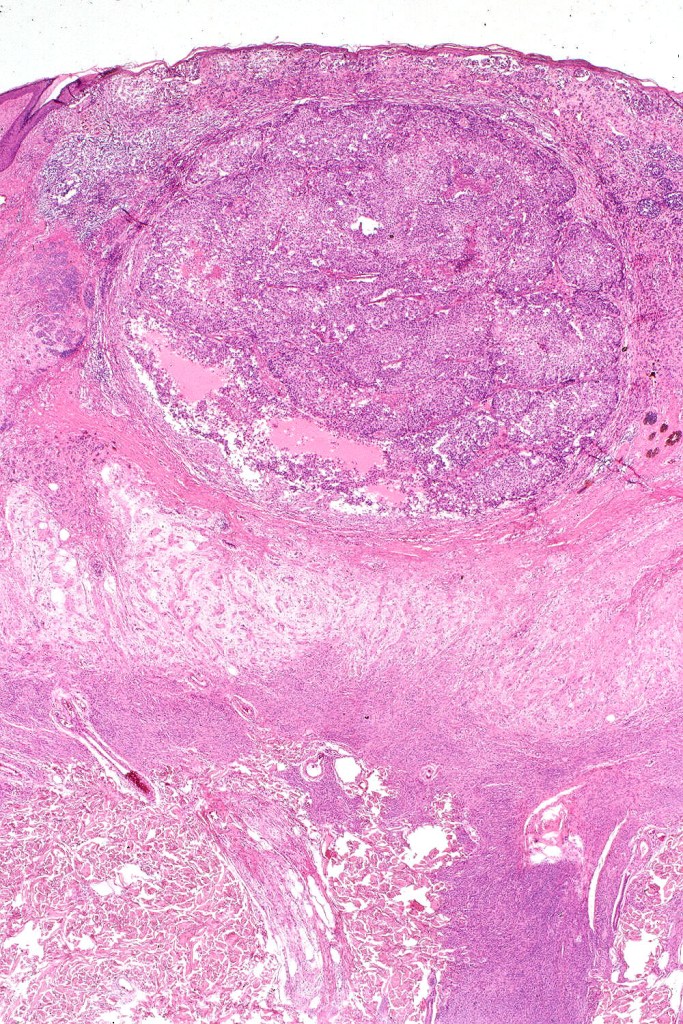

Histological features

•Most often are distinctive at scanning/low power examination due to the depth of involvement

•Hyperkeratosis, acanthosis and commonly papillomatosis

•Nested junctional component & nests within the papillary dermis

•Diffuse infiltrate of nevus cells often extending deeply into the dermis or beyond, single filing is often present at base & may involve the septa of the subcutaneous fat

•Involvement of appendages & arrector pili muscles

•Neurotization, neurofibroma-like lesions & neurocristic hamartoma

•Perineural sheath infiltration

•Blood vessel and lymphatic wall infiltration

•Superficial mitotic activity

This melanoma arose in a small congenital nevus of the scalp. It metastasized widely. Varying features in different fields.